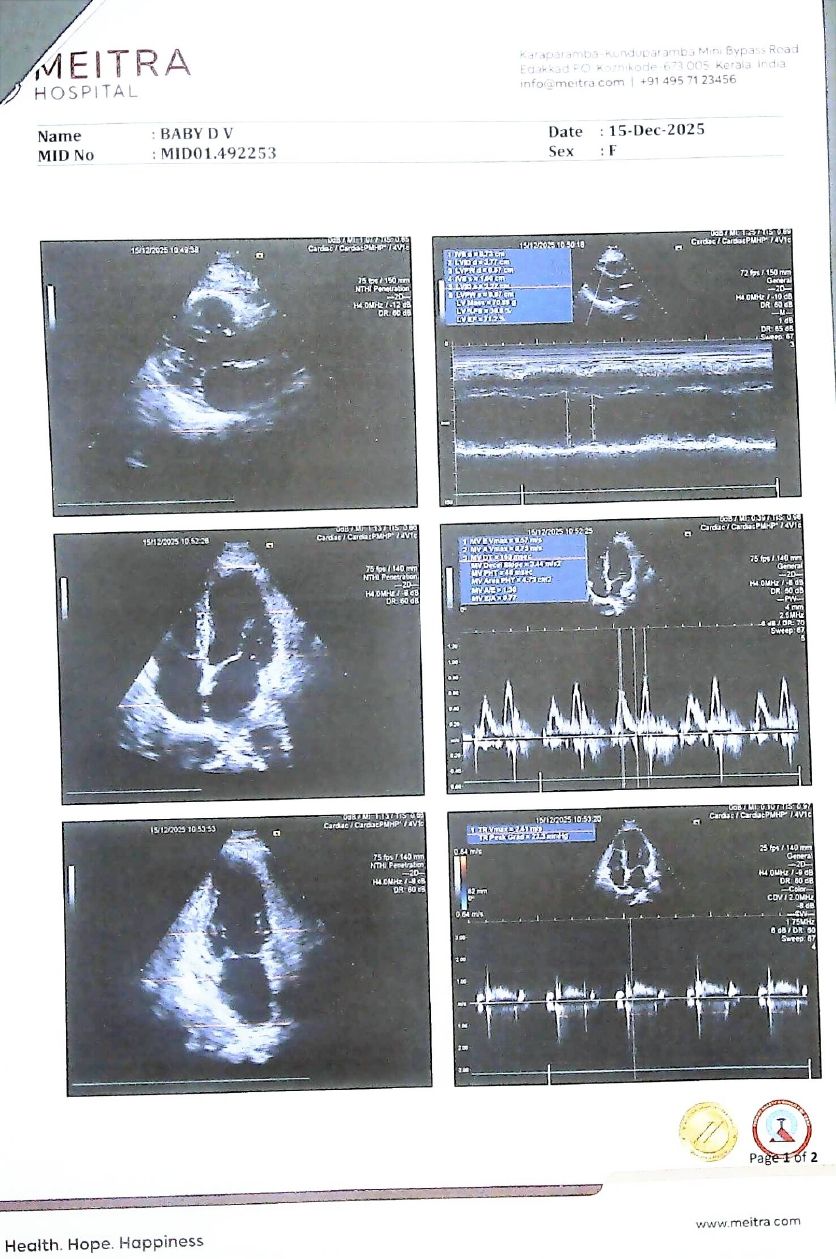

Echocardiography – After Ayurveda Treatment

- Normal left ventricular wall motion

- No regional wall motion abnormality

- Normal LV systolic function

- Improved diastolic function

- No significant mitral regurgitation

- No pulmonary hypertension

Comparative Echocardiography Findings

| Parameter | Before Treatment (02.09.2024) | After Treatment |

|---|---|---|

| Regional wall motion abnormality | Present | Absent |

| LV apex | Hypokinetic | Normal |

| LV systolic function | Fair | Normal |

| Diastolic function | Grade I dysfunction | Improved |

| Mitral regurgitation | Mild | Absent |

| Pulmonary hypertension | Absent | Absent |